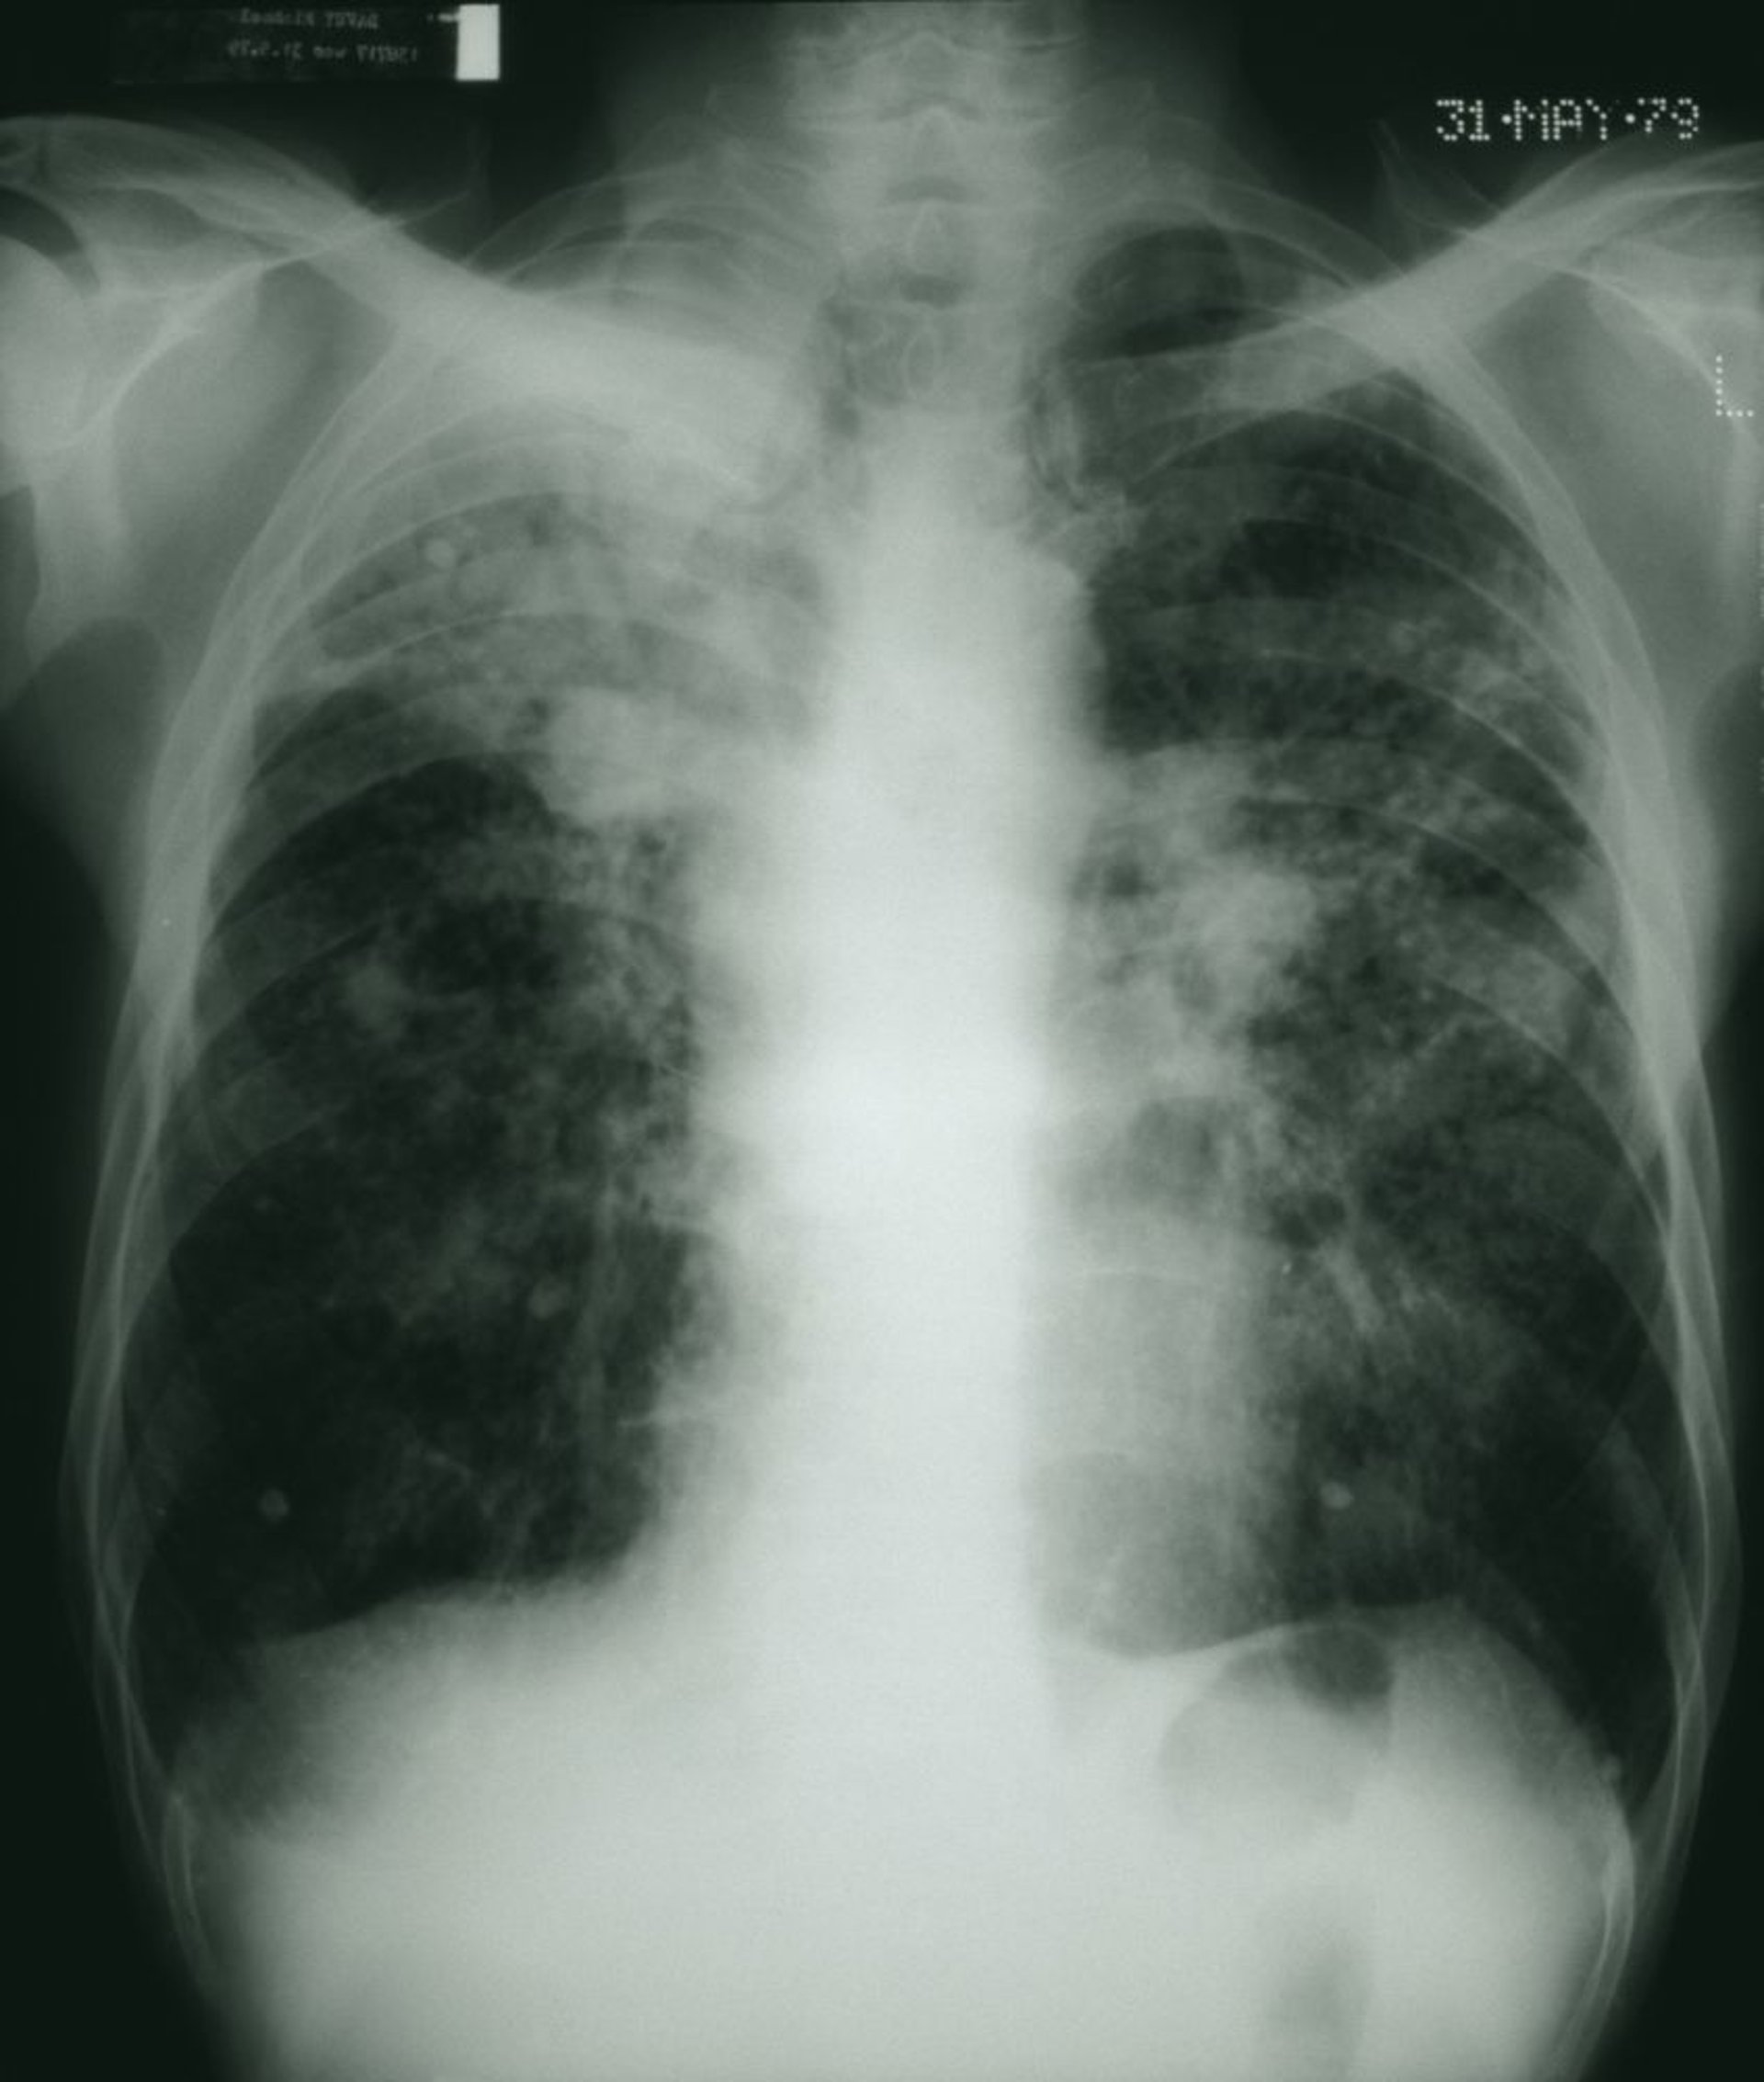

Пневмокониоз

Темные легочные поля имеют неравномерный рисунок с вкраплениями белых волокнистых масс, что соответствует прогрессирующему пневмокониозу работников угольной промышленности.